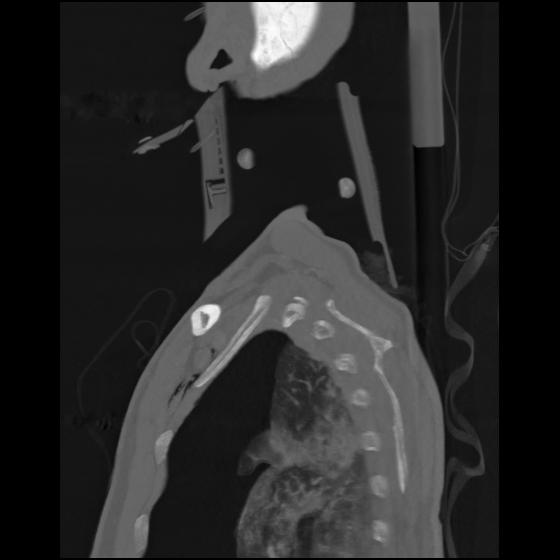

24 ANGIO,CE,Sag-MIP,5.000,ANGIO,Sag-MIP,